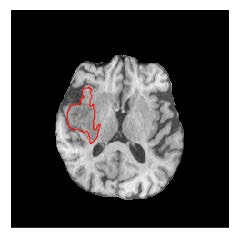

Machine learning has been widely adopted for medical image analysis in recent years given its promising performance in image segmentation and classification tasks. The success of machine learning, in particular supervised learning, depends on the availability of manually annotated datasets. For medical imaging applications, such annotated datasets are not easy to acquire, it takes a substantial amount of time and resource to curate an annotated medical image set. In this paper, we propose an efficient annotation framework for brain MR images that can suggest informative sample images for human experts to annotate. We evaluate the framework on two different brain image analysis tasks, namely brain tumour segmentation and whole brain segmentation. Experiments show that for brain tumour segmentation task on the BraTS 2019 dataset, training a segmentation model with only 7% suggestively annotated image samples can achieve a performance comparable to that of training on the full dataset. For whole brain segmentation on the MALC dataset, training with 42% suggestively annotated image samples can achieve a comparable performance to training on the full dataset. The proposed framework demonstrates a promising way to save manual annotation cost and improve data efficiency in medical imaging applications.